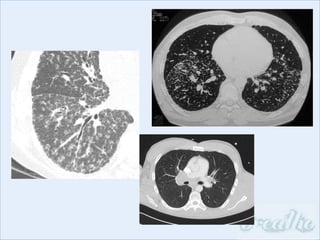

Imaging: bihilar and mediastinal lymphadenopathy,

micronodular infiltrates (peri-lymphatic), airspace-like

opacities, ground-glass opacities, peripheral

cavitation, fibrosis

Investigations Bloods: serum ACE(increased in up to 80%), hypercalcaemia in 2-5%, increased ALP if liver infiltration Lung function tests: mixed obstructive/restrictive defect, reduced transfer factor Imaging: bihilar and mediastinal lymphadenopathy, micronodular infiltrates (peri-lymphatic), airspace-like opacities, ground-glass opacities, peripheral cavitation, fibrosis Bronchoscopy: EBUS to sample lymph nodes, bronchial and transbronchial biopsies Tissue biopsy: skin lesions, parotids, extrathoracic lymph nodes, liver